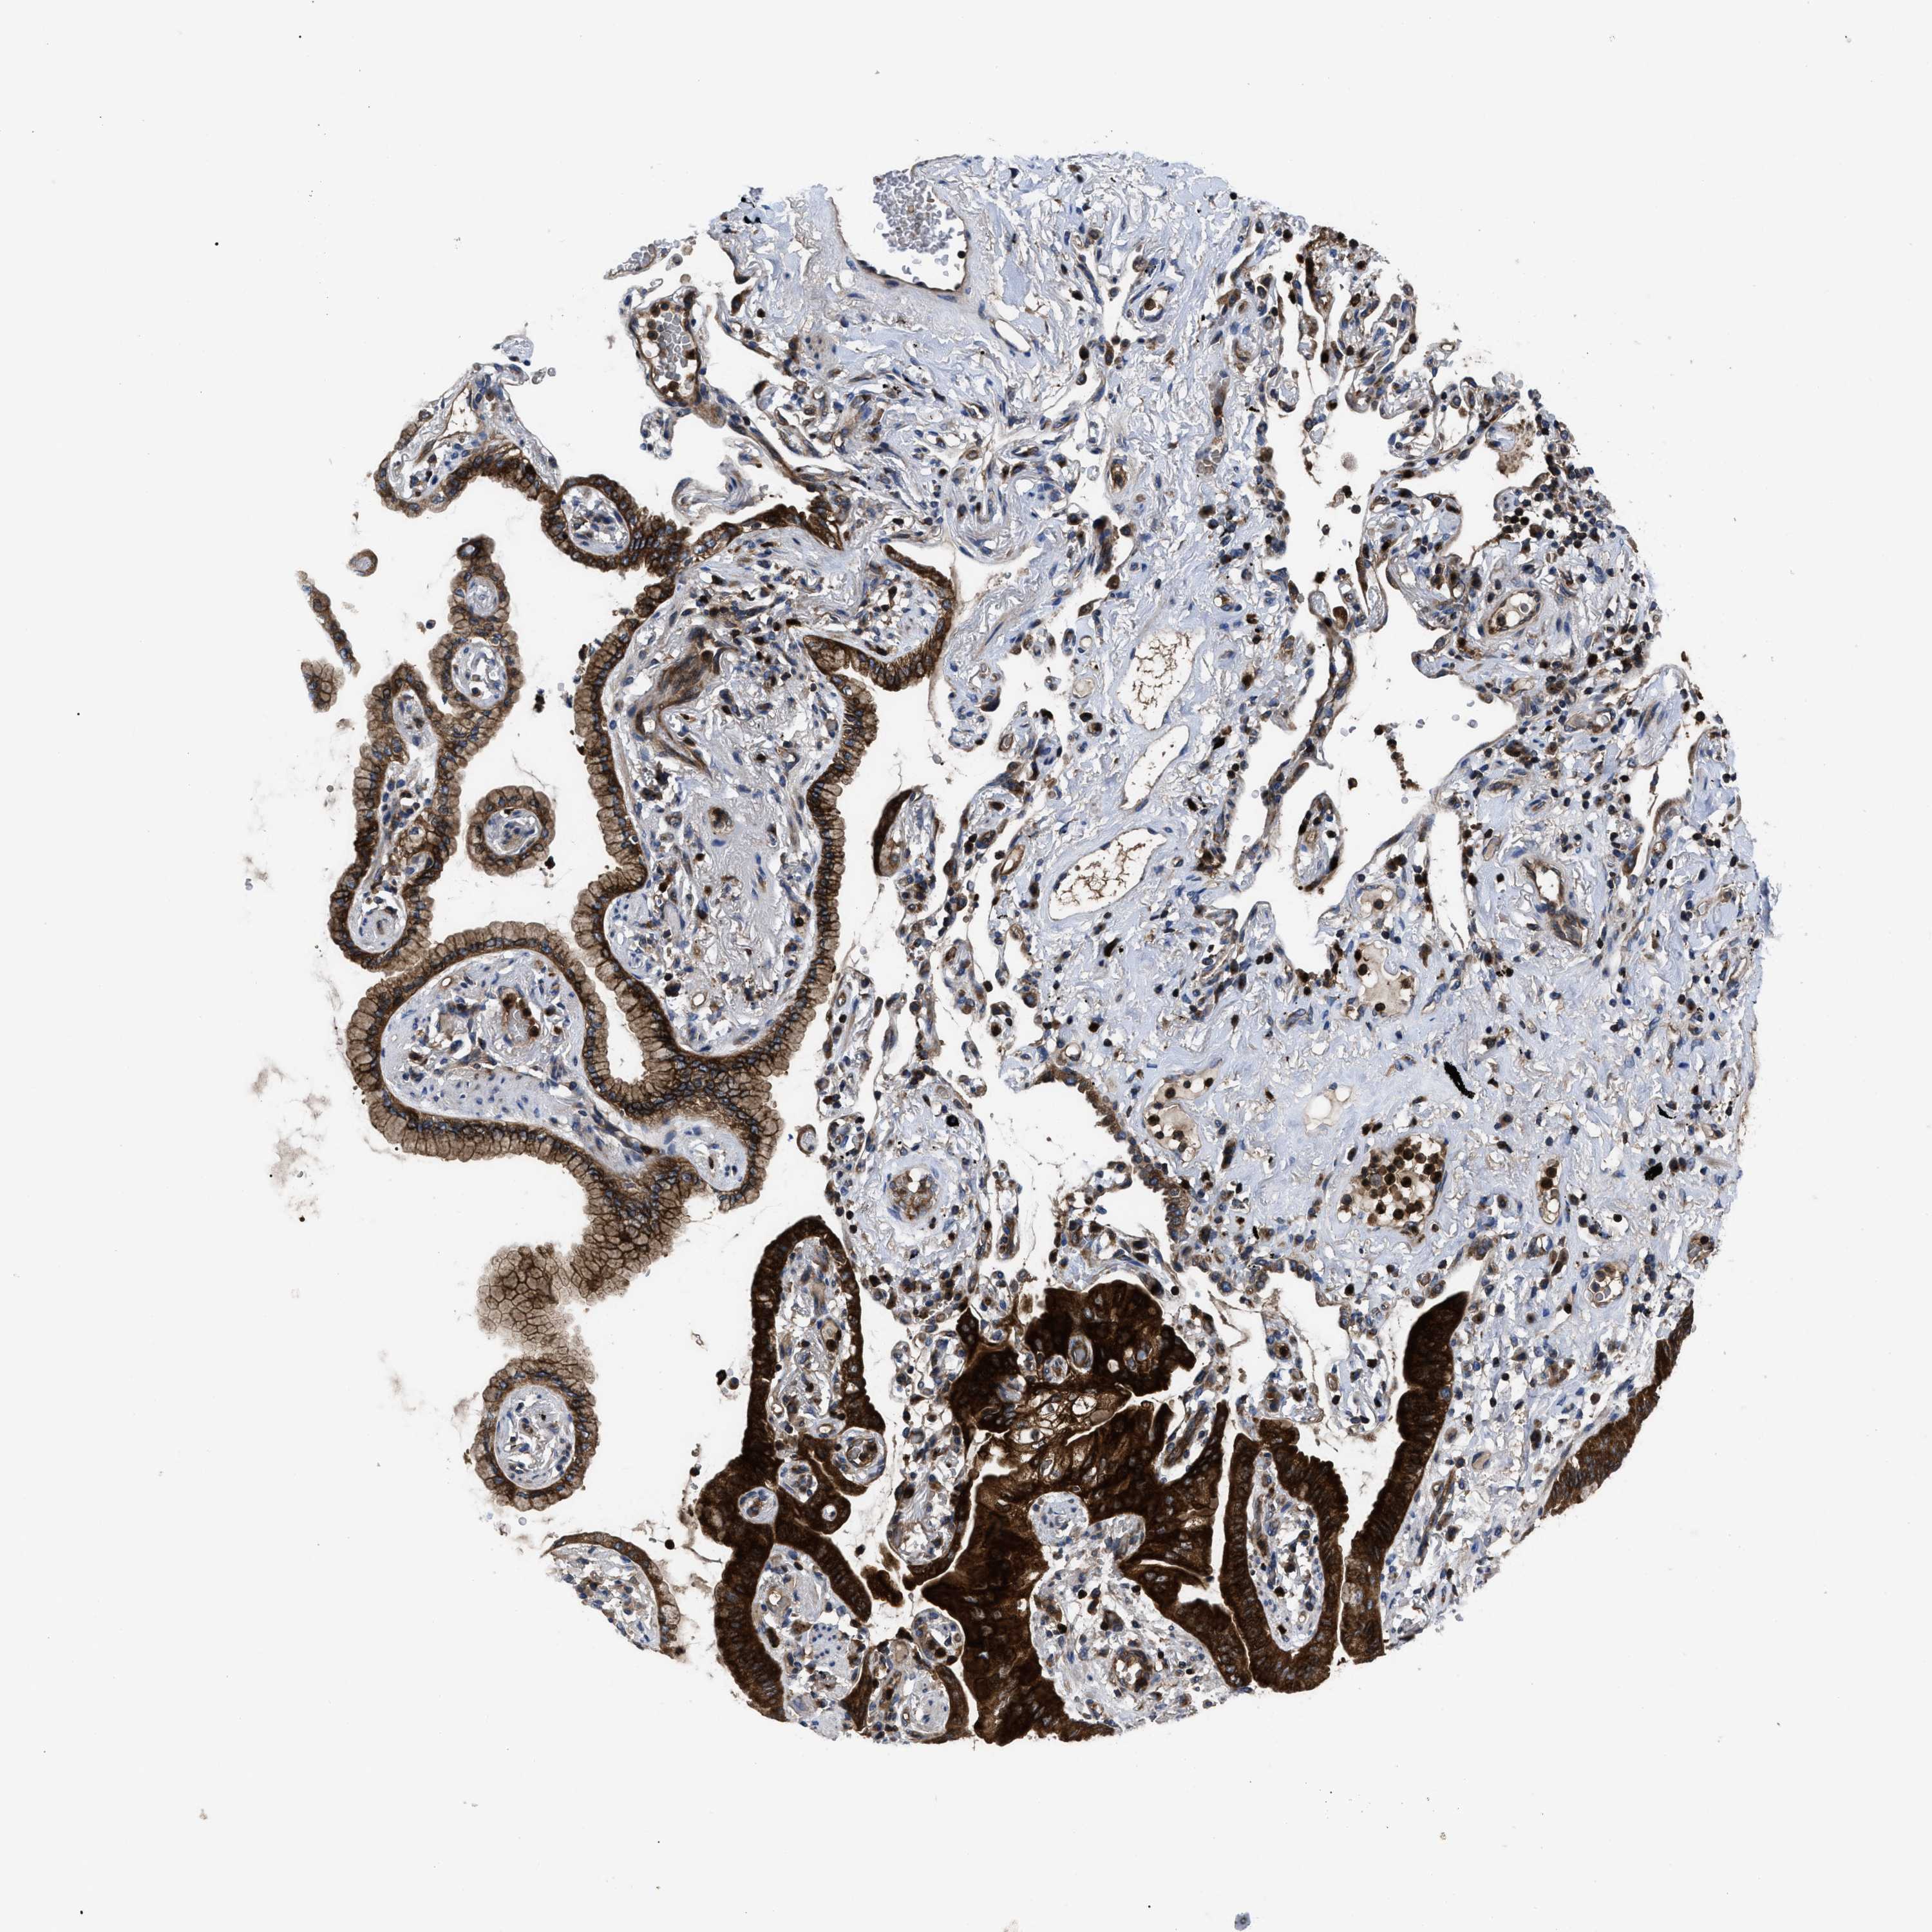

LUNG ADENOCARCINOMA (VALIDATION) - Interactive survival scatter ploti

The Survival Scatter plot shows the clinical status (i.e. dead or alive) for all individuals in the patient cohort, based on the same data that underlies the corresponding Kaplan-Meier plots. Patients that are alive at last time for follow-up are shown in blue and patients who have died during the study are shown in red.

The x-axis shows the expression levels (FPKM) of the investigated gene in the tumor tissue at the time of diagnosis. The y-axis shows the follow-up time after diagnosis (years). Both axes are complimented with kernel density curves demonstrating the data density over the axes. The top density plot shows the expression levels (FPKM) distribution among dead (red) and alive patients (blue). The right density plot shows the data density of the survived years of dead patients with high and low expression levels respectively, stratified using the cutoff indicated by the vertical dashed line through the Survival Scatter plot. This cutoff is automatically defined based on the FPKM cutoff that minimizes the p-score. The cutoff can be changed by dragging the vertical line or by entering a cutoff value in the square labeled "Current cut-off".

Under the Survival Scatter plot the p-score landscape (black curve; left axis) is shown together with dead median separation (red curve; right axis). Dead median separation is the difference in median mRNA expression between patients who have died with high and low expression, respectively. It is calculated as follows: median FPKM expression of dead patients with high expression - median FPKM expression of dead patients with low expression. This is intended to aid the user in visually exploring custom cutoffs and the associated p-scores and dead median separation.

Individual patient data is displayed and can be filtered by clicking on one or more of the category buttons on the top of the page. Categories describing expression level and patient information include: high, low, alive, dead, female, male and tumor stages. The scale of the x-axis can be toggled between linear and log-scale by clicking on the "x log" button. Mouse-over function shows TCGA ID, patient information and mRNA expression (FPKM) for each patient.

& Survival analysisi

Kaplan-Meier plots summarize results from analysis of correlation between mRNA expression level and patient survival. Patients were divided based on level of expression into one of the two groups "low" (under cut off) or "high" (over cut off). X-axis shows time for survival (years) and y-axis shows the probability of survival, where 1.0 corresponds to 100 percent.

YBEY is not prognostic in Lung Adenocarcinoma (validation)

Best expression cut offi

Based on the FPKM value of each gene, patients were classified into two groups and association between prognosis (survival) and gene expression (FPKM) was examined. The best expression cut-off refers the FPKM value that yields maximal difference with regard to survival between the two groups at the lowest log-rank P-value. Best expression cut-off was selected based on survival analysis .

When clicking on this number, the vertical dashed line indicating cut-off, the interactive survival plot, and the Kaplan-Meier curve will be adjusted to show results based on the best expression cut-off.

: 18

P scorei

Log-rank P value for Kaplan-Meier plot showing results from analysis of correlation between mRNA expression level and patient survival.

N/A

TCGA RNA samplesi

RNA-seq data is reported as average FPKM (number Fragments Per Kilobase of exon per Million reads), generated by the The Cancer Genome Atlas (TCGA) .

Normal distribution across the dataset is visualized with box plots, shown as median and 25th and 75th percentiles. Points are displayed as outliers if they are above or below 1.5 times the interquartile range. FPKM values of the individual samples are presented next to the box plot.

Average pTPM 14.8

Number of samples 105